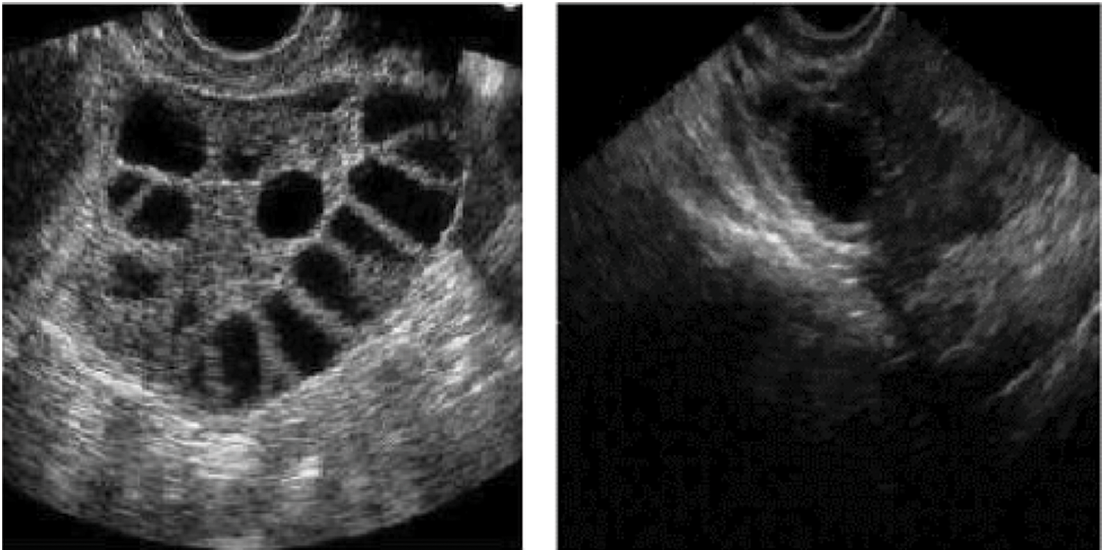

The disorder known as PCOS or polycystic ovarian syndrome is characterized by an abundance of primitive follicles in the ovary. This condition is detected through ultrasound scans that provide crucial details on the size and the number of ovarian follicles. Oocytes (eggs) grow in ovarian follicles, which are round, fluid-filled entities. Ovarian follicles showed up as dark, approximately round areas in two-dimensional ultrasound imaging. An ovary with 12 or even more follicles that are at least 2 mm in diameter and/or 10 cm3 in volume is considered to have PCOS. A good female’s uterus system depends on the quantity and size of her follicles, particularly if she’s attempting to get pregnant. Scanning with ultrasonography is non-intrusive, transportable, and reasonably priced.

As a result, ovarian ultrasound has emerged as a useful method for identifying ovarian follicles and diagnosing PCOS. Therefore, speckle noise in ultrasonic imaging results in poor image quality. This disruption makes it difficult for medical professionals to employ manual diagnostics to identify ovarian follicles. Manual assessment and classification are time-consuming, difficult, and frequently inaccurate. So the proposed deep-learning-based automatic diagnosis helps to reduce manual errors and also improves classification accuracy.

In this research obstetrician-gynecologist (OB-GYN) is used to learn more about the assessment metrics that physicians often seek within medical applications before deciding on the assessment metric to use for the wrappers. Following a detailed debate, it became obvious that lowering the frequency of false positives (FP) is crucial to preventing patients from receiving treatments that are more harmful than helpful. Fig. 4 shows the PCOS samples used for classification. This research uses python 3.4 for implementation in the windows 64-bit operating system.

Figure 4: Sample PCOS dataset from Kaggle